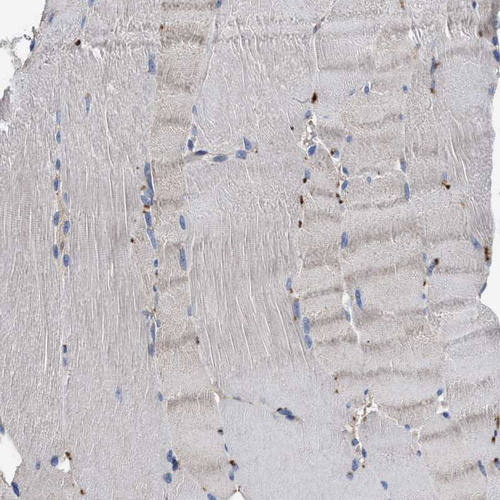

Immunohistochemical staining of human testis shows moderate to strong granular cytoplasmic positivity in seminiferous ducts.